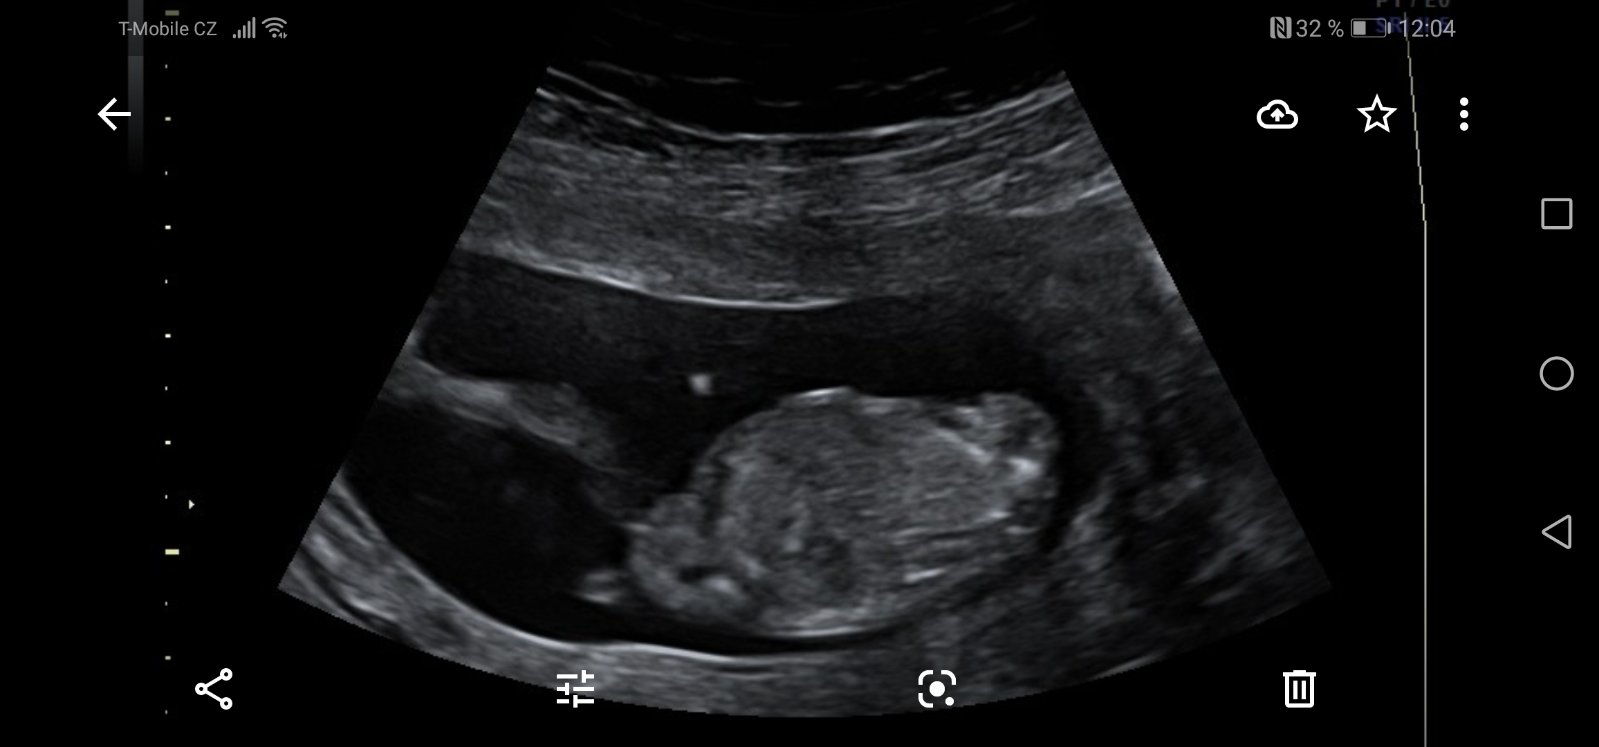

Je to holčička nebo chlapeček? Foto ultrazvuku

Ahoj maminky a budoucí maminky 😉 Prosím, poradila byste mi některá, co vidíte na fotce z ultrazvuku ve 20. týdnu za pohlaví? Určitě jste foteček viděly už mraky, proto vás žádám o radu...Nechci nikoho ovlivnit, proto svůj tip řeknu později 🙂 Děkuju moc!!!

@sebinka123 řekla bych holka, jinou fotku nemáte? Leží tam trochu nakřivo 🙂

@kajda3 ještě možná tuhle, tady přirození trochu je vidět, po přiblížení. Prý ty pysky jsou taky hodně velké. Prostě nevím. 😥